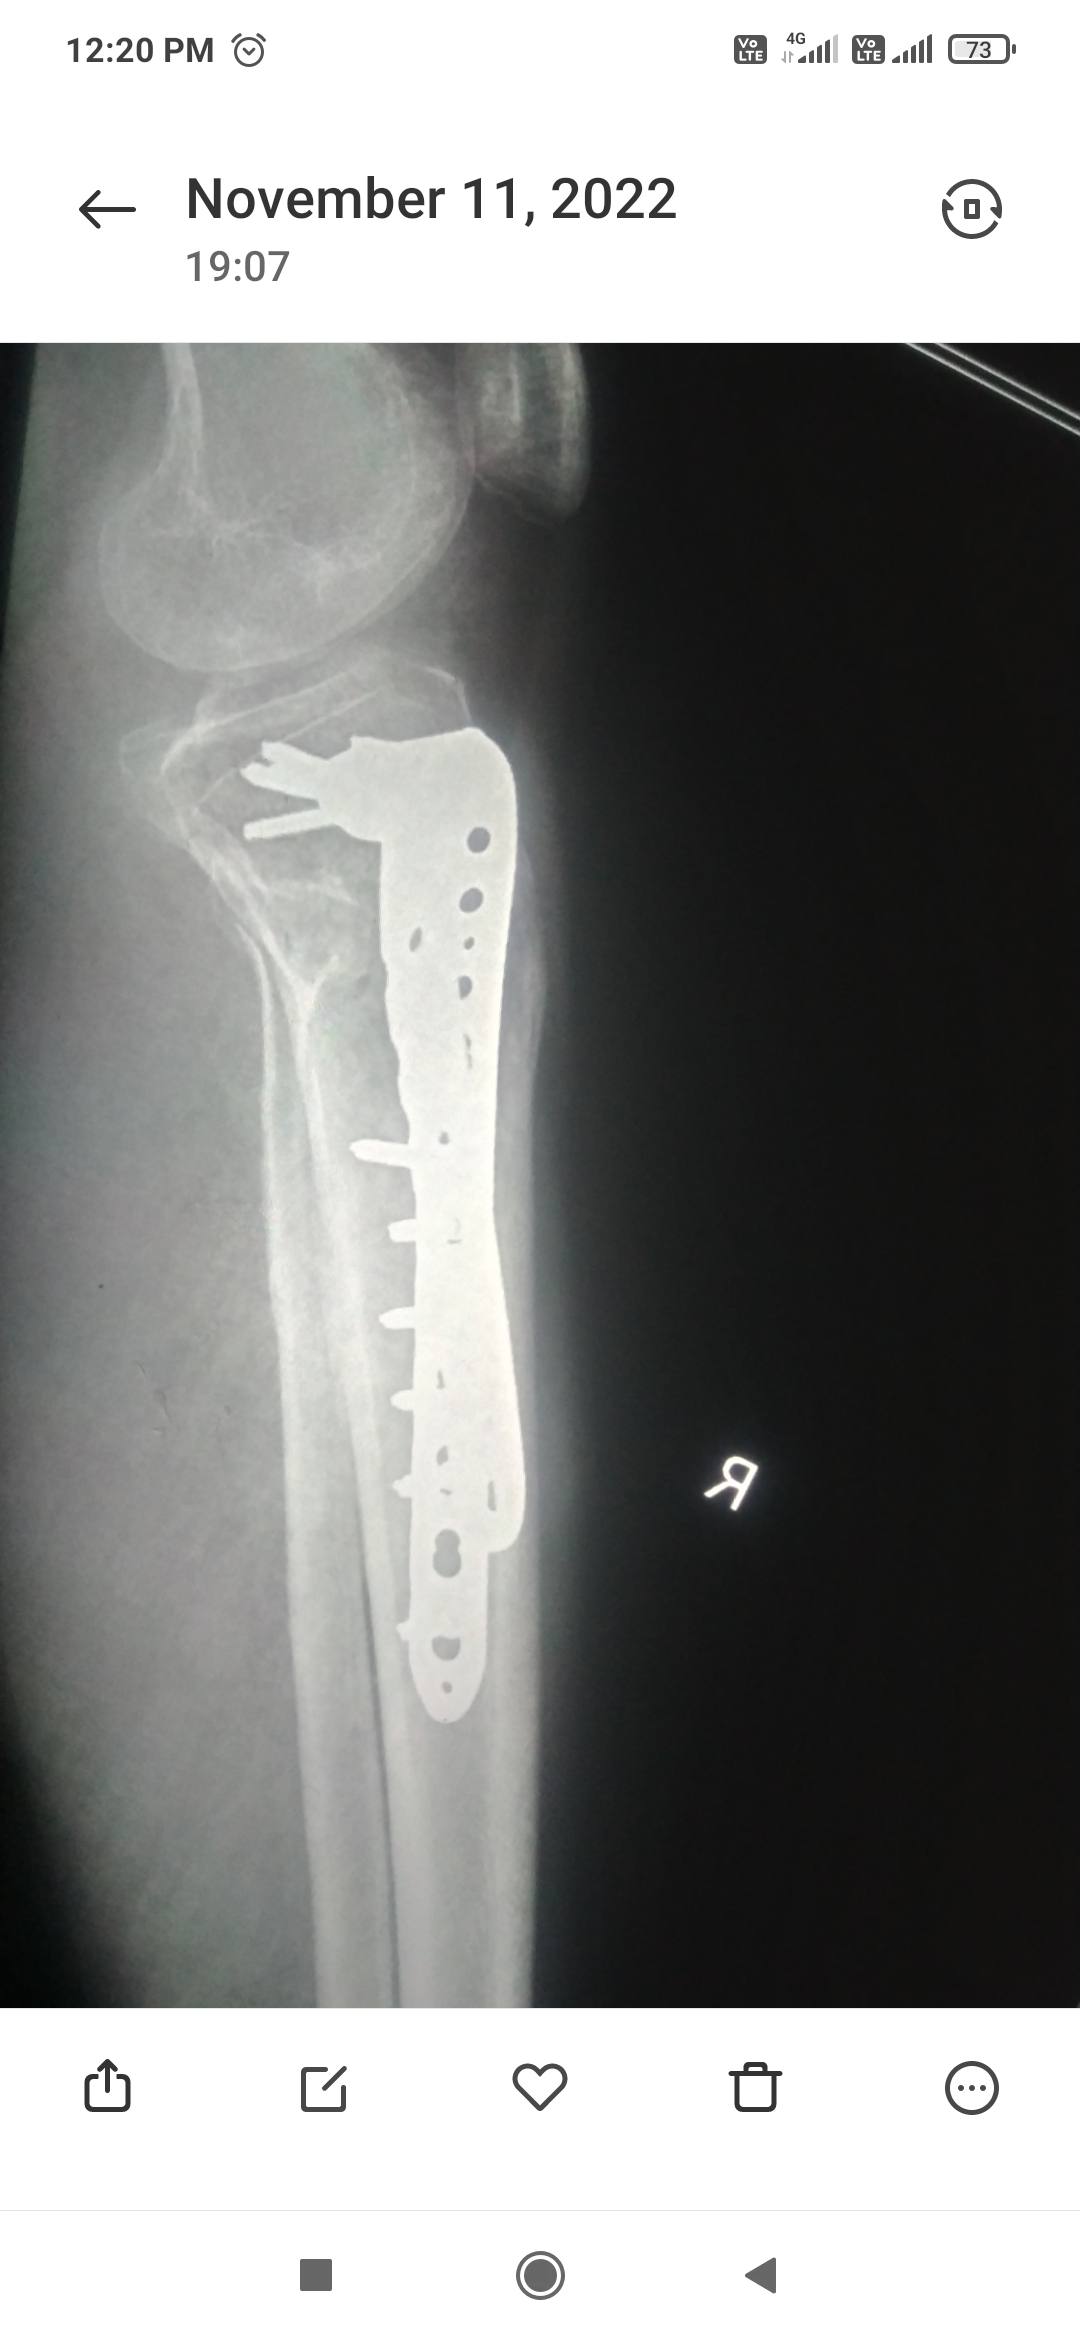

. Following